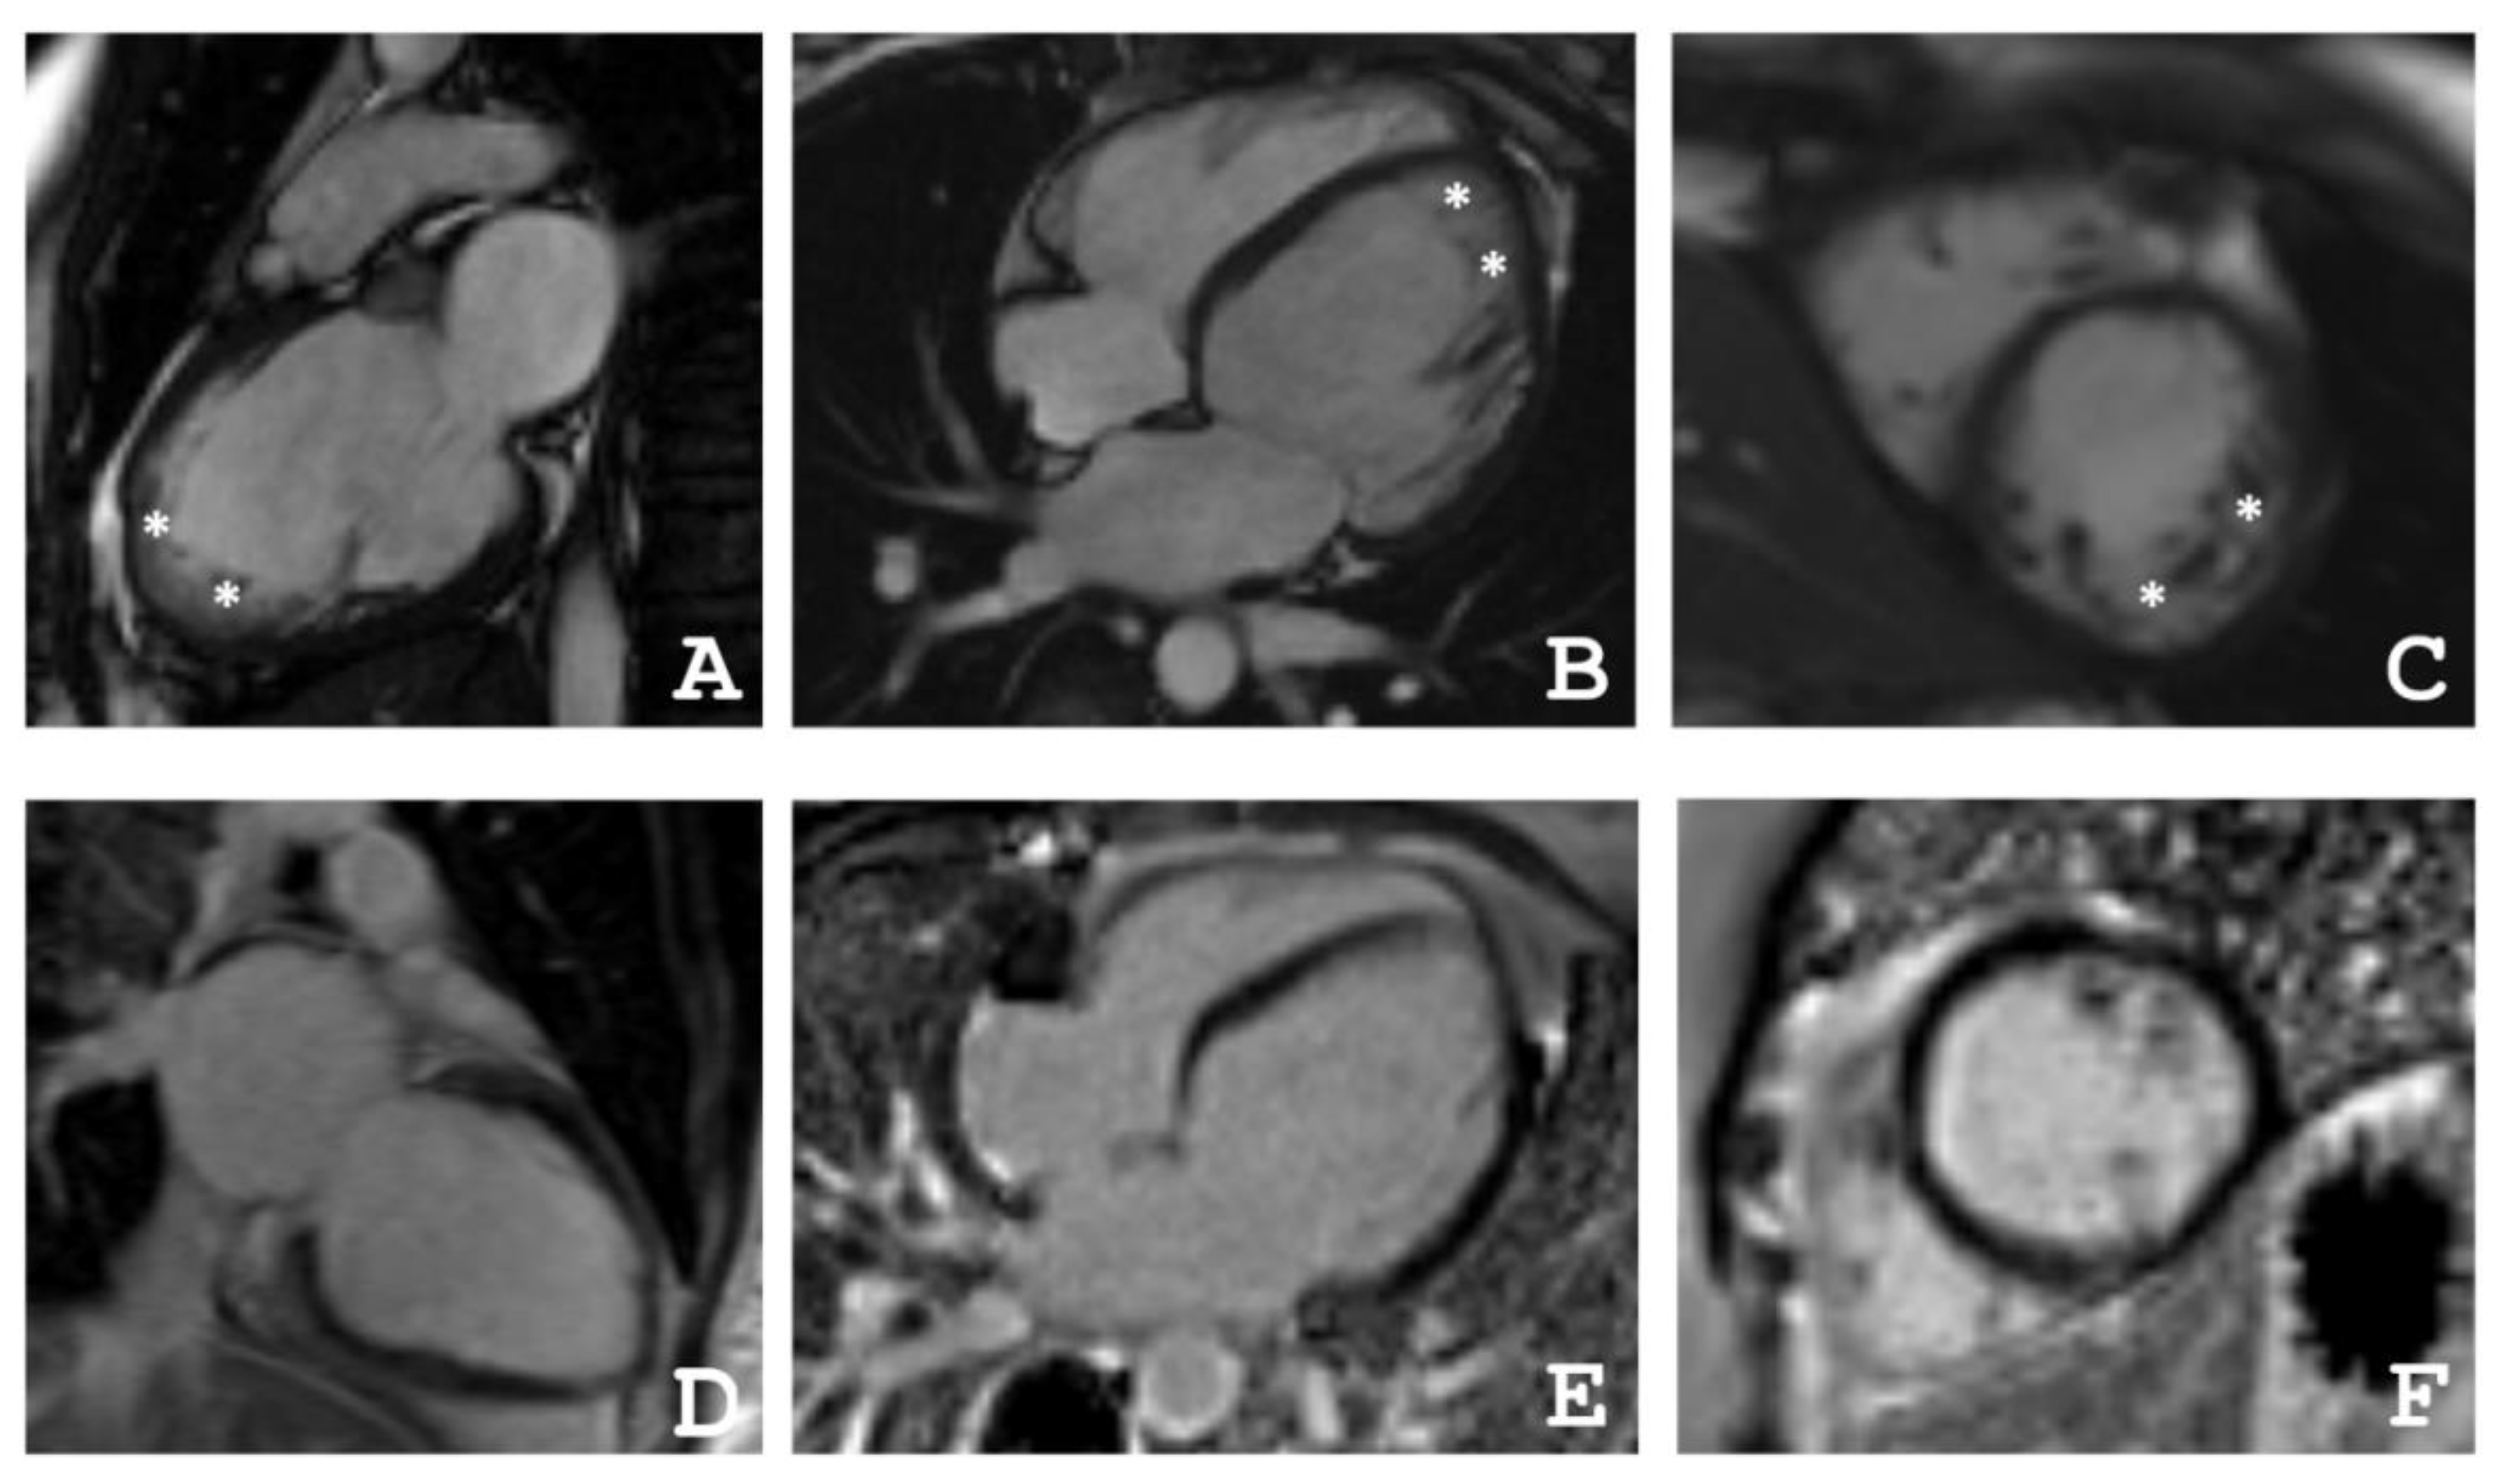

2.1. Clinical Investigations

4.2. Cardiac Magnetic Resonance Imaging